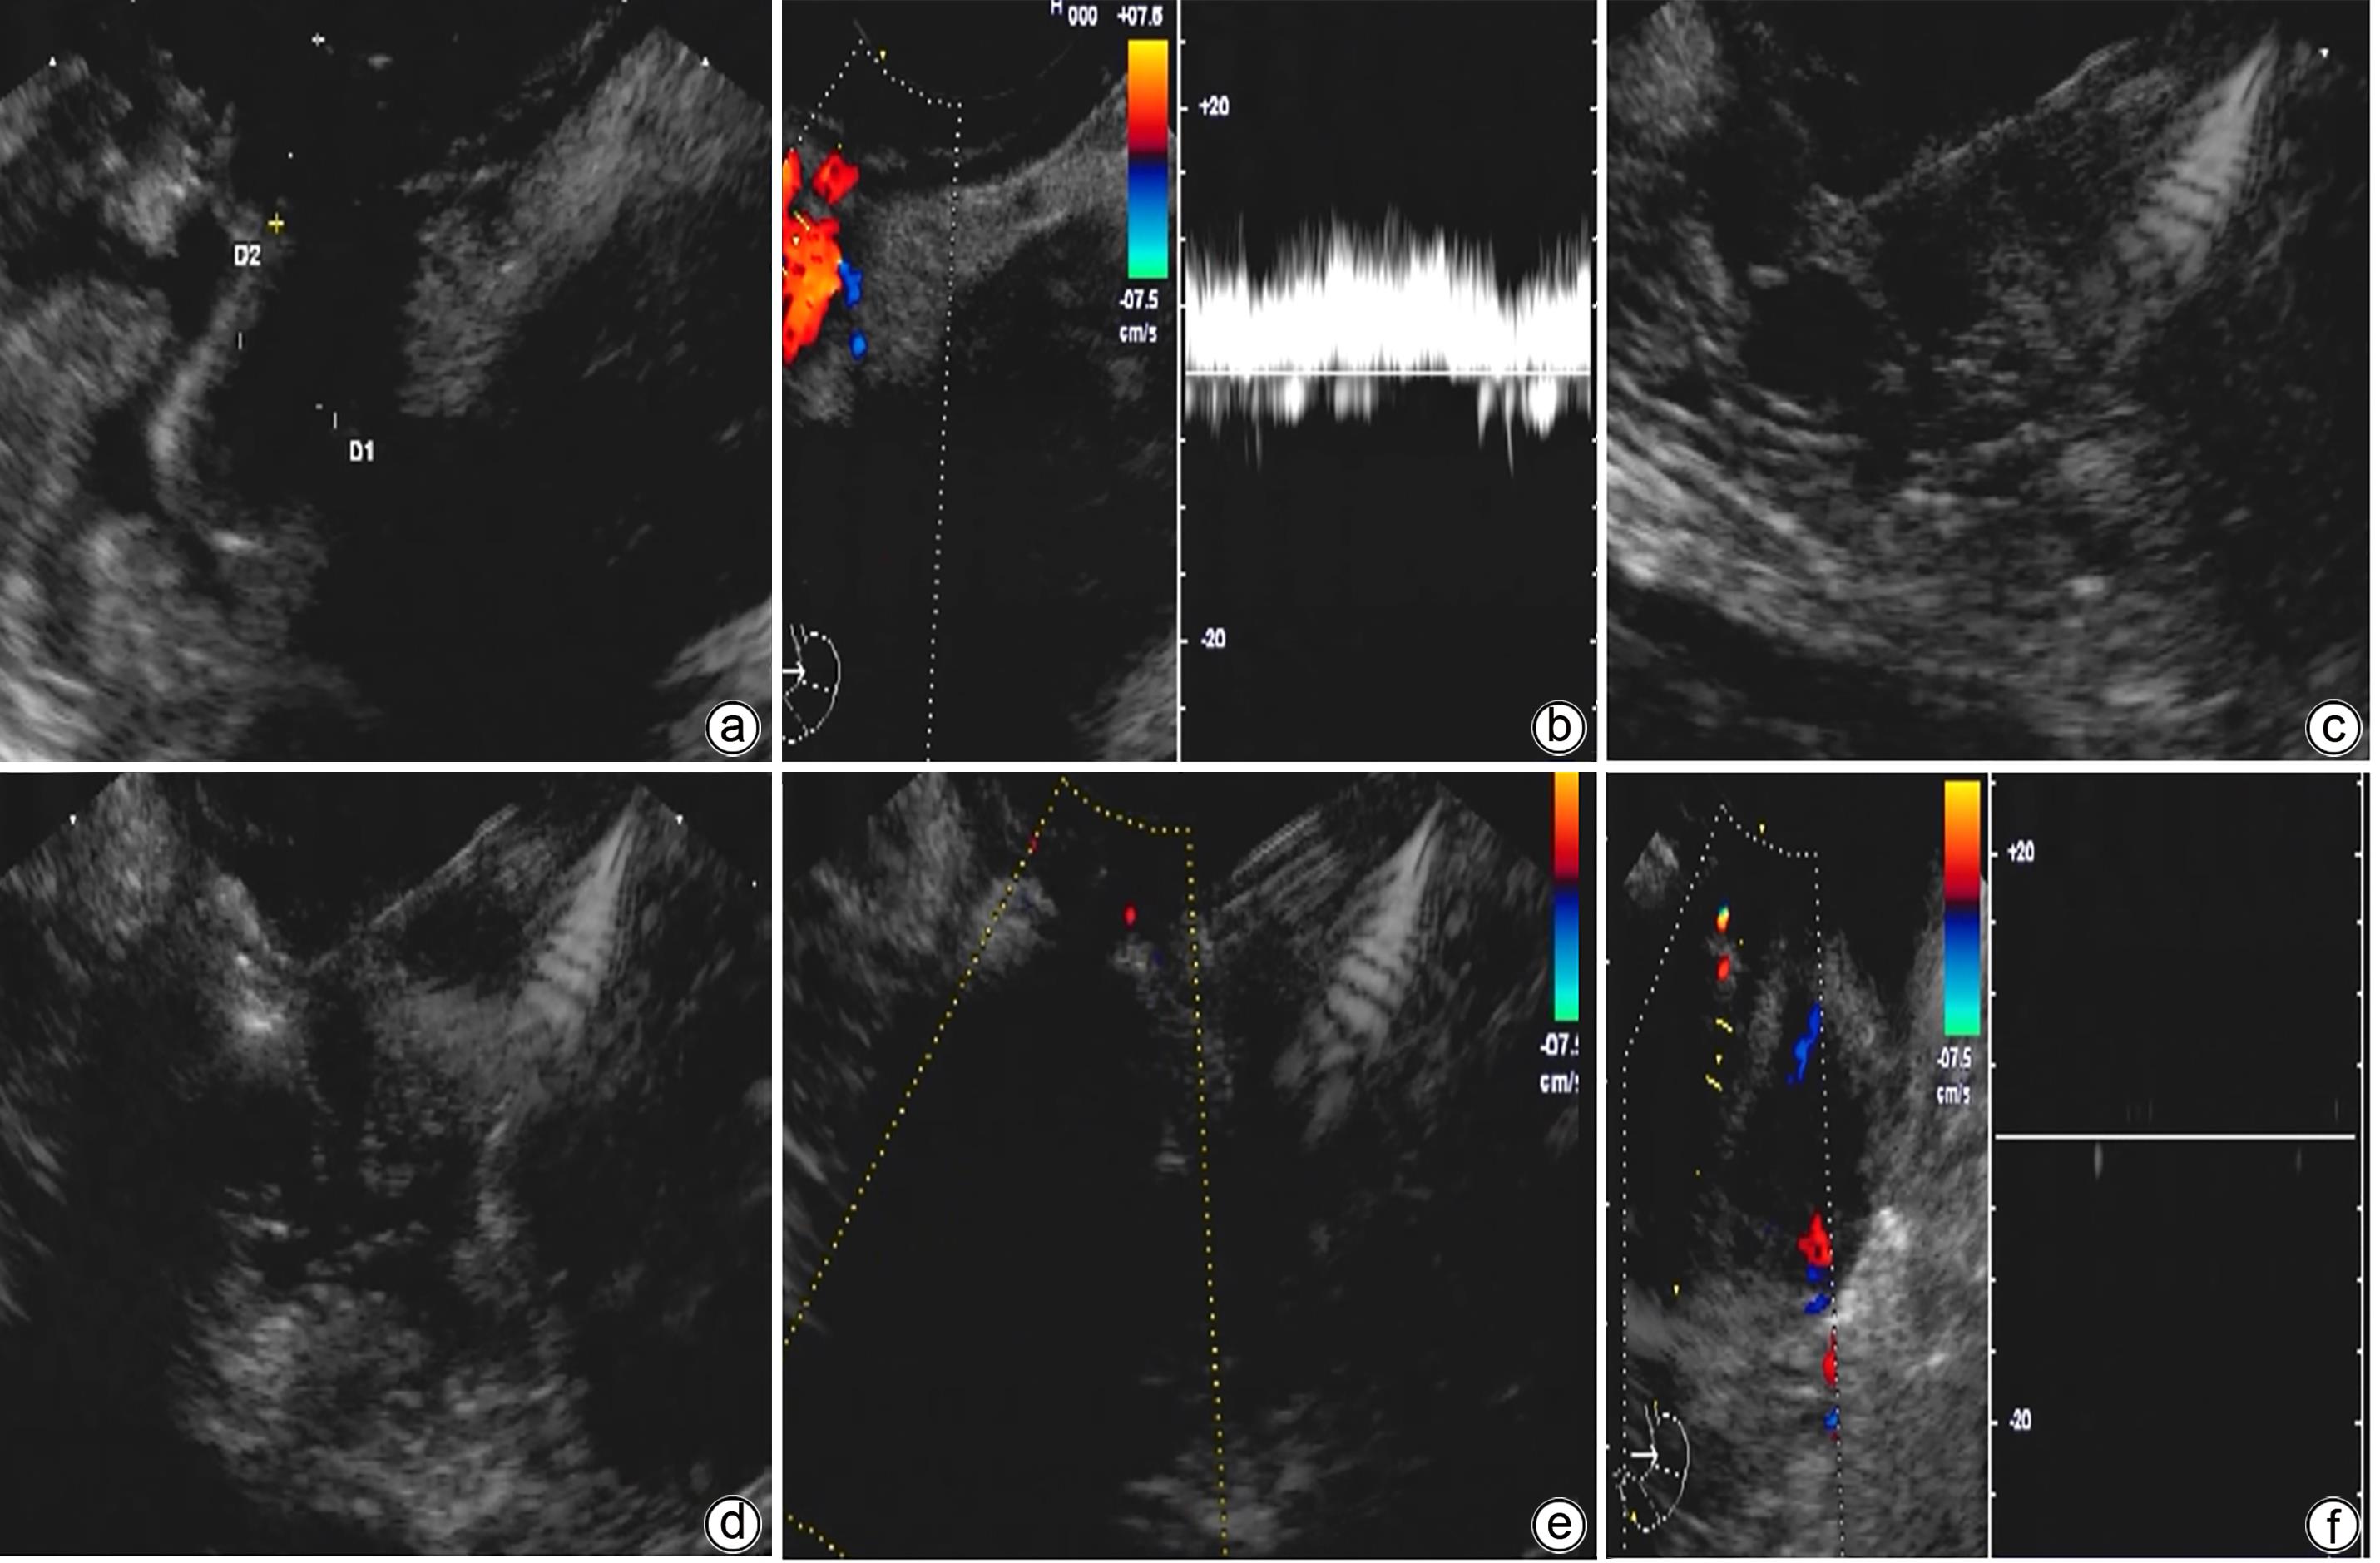

摘要:

目的  探讨金属夹辅助内镜超声引导组织胶注射治疗合并胃肾分流的胃静脉曲张患者的效果及安全性。  方法  纳入2023年2月—2023年6月因肝硬化伴胃静脉曲张于首都医科大学附属北京地坛医院就诊,证实存在胃肾分流(GRS),并接受金属夹辅助内镜超声引导组织胶注射治疗的患者。主要的评价指标是术后曲张静脉减轻或消失情况,次要评价指标为手术完成情况及并发症。  结果  共11例合并GRS的胃静脉曲张患者纳入研究,男7例,女4例;中位年龄55岁;肝功能Child-Pugh A级1例,Child-Pugh B级7例,Child-Pugh C级3例;分流道最大直径(中位)8 mm,最小直径(中位)4 mm。治疗前靶血管血流中位流速11 cm/s,金属夹阻断后靶血管中位流速5 cm/s;中位组织胶使用量2 mL,聚桂醇使用量均为1 mL。所有患者手术结束后血流信号100%消失,手术成功率100%。随访6周患者均无再出血发生。术后1个月复查胃镜示静脉曲张根除或基本消失9例,静脉曲张改善2例。  结论  对于合并GRS的胃静脉曲张肝硬化患者,金属夹辅助内镜超声引导组织胶注射治疗是一种可行,安全,有效的方法。